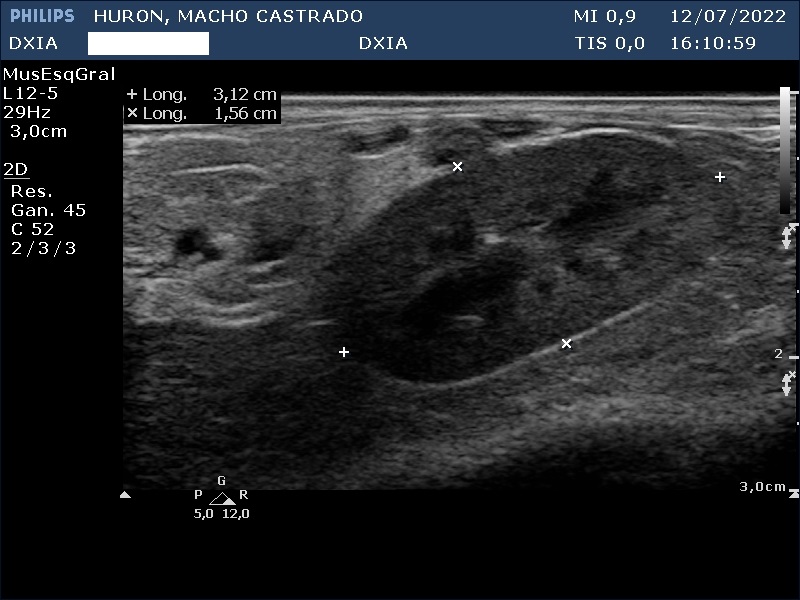

Estudio de ecografía abdominal

En esta ocasión os queremos presentar el caso de hurón (macho castrado) al que, debido a los síntomas que presentaba, tuvimos que realizarle un estudio ecográfico abdominal.

Presenta convulsiones así como hipoglucemias con picos de hiperglucemia por lo que su veterinario decide realizar un estudio de ecografía abdominal.

Hallazgos ecográficos